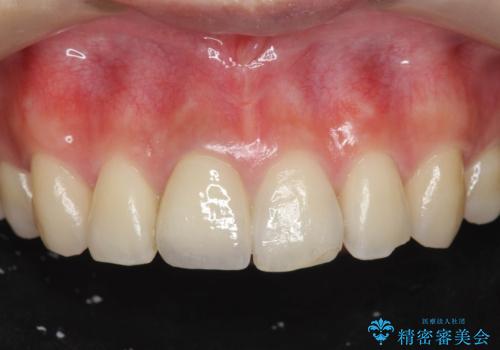

前歯の変色 打撲により失活した前歯の根管・セラミック治療

自然な色調をセラミッククラウンで再現することができ、審美性の改善に大変喜んでいただくことができました。